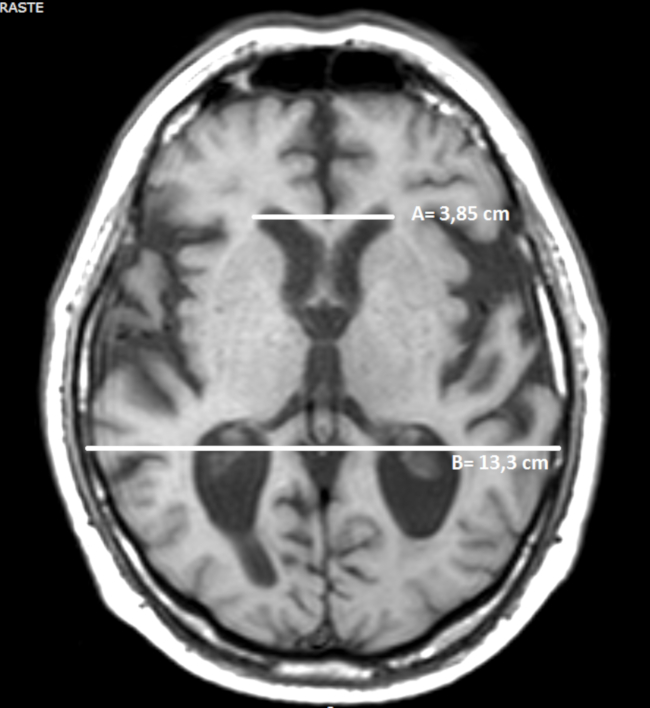

Para llevar a la práctica este método de medición del volumen de los hematomas intraparenquimatosos mediante una TC de cerebro, se elige el corte con el área de mayor sangrado, midiéndose el máximo diámetro anteroposterior del mismo (parámetro A). El parámetro B corresponde al diámetro transversal de la lesión en ese mismo corte.3,4,7 El parámetro C es el número de cortes en los que se aprecia sangrado multiplicado por el espesor de corte (►Fig. 1).1,3,4,7

La fórmula es: A x B x C /2 y el resultado final se expresa en centímetros cúbicos.1

A) Índice bicaudado: se obtiene dividiendo la distancia mínima de los ventrículos laterales a nivel de las cabezas de los núcleos caudados con el diámetro del cráneo a ese mismo nivel (►Fig. 4).

B) Índice de Evans: se calcula dividiendo el diámetro máximo de las astas frontales de los ventrículos laterales con el diámetro máximo intracraneal en el mismo corte a la altura de los forámenes de Monro (►Fig. 5).22,23,24

Un valor > a 0,30 indica ventriculomegalia y puede considerarse patológico, pero no puede discriminarse la etiología por atrofia u otra entidad.22,23,24

C) Índice bifrontal: se calcula dividiendo el diámetro máximo de las astas frontales de los ventrículos laterales y el diámetro intracraneal a ese mismo nivel (►Fig. 6).22,23,24